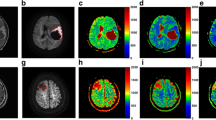

The ROC curve analyses for different combinations of data for distinguishing tumor recurrence from non-recurrence are shown in Fig. 1. The AUC of the combination of BT-RADS + DSC PWI was similar to that of the combination of BT-RADS + DWI (0.90 vs. 0.88, respectively, Z = 0.52, p = 0.61). The AUCs of both combinations were significantly larger than that of BT-RADS alone (0.90 vs. 0.76, Z = 3.35, p < 0.01; 0.88 vs. 0.76, Z = 2.73, p < 0.01, respectively). The diagnostic performance of BT-RADS was significantly improved when it was combined with rCBVmax (DSC PWI) and ADCmean (DWI) (AUC = 0.95; 95% CI 0.88–0.98), and their combination of BT-RADS + DSC PWI + DWI manifested the best diagnostic performance for distinguishing tumor recurrence from non-recurrence (p < 0.05 for any comparison with the other combinations). The cutoff values of rCBVmax and ADCmean utilized to the differentiation of tumor recurrence and non-recurrence were 1.6, 1.0 × 10−3 mm2/s, respectively (Table 2). Typical cases of tumor recurrence and non-recurrence are shown in Fig. 2 and Fig. 3, respectively. The AUC, accuracy, sensitivity, specificity, PPV, and NPV of each combination of MR data are summarized in Table 3, in which the combination of BT-RADS + DSC PWI + DWI exhibited the highest accuracy (0.92), sensitivity (0.98; 95% CI 0.88–0.99), and NPV (0.97; 95% CI 0.83–0.99).

A 54-year-old female with IDH wildtype anaplastic astrocytoma. a No abnormal enhancement was found 10 months after completing radiotherapy on Gd-enhanced T1 weighted image (Gd-T1WI). b Gd-T1WI showed asymmetric new enhanced lesion defined as Category 3b (arrow) in the left frontal lobe 16 months after completing radiotherapy. c DSC PWI showed hyperperfusion (arrow) in the left frontal lobe. d,e Restricted diffusion was observed in the enhanced lesion on DWI and ADC map (arrow). f The enhancement further enlarged with an increased mass effect 19 months after completing radiotherapy on Gd-T1WI. Consequently, the enhanced lesion in the left frontal lobe was deemed a tumor recurrence

A 37-year-old female with anaplastic oligodendroglioma with IDH mutation and 1p/19q co-deletion. a No abnormal enhancement was found 24 months after completing radiotherapy on Gd-enhanced T1 weighted image (Gd-T1WI). b Gd-T1WI showed asymmetric new enhanced lesion defined as Category 3b (arrow) in the right frontal lobe 27 months after completing radiotherapy. c DSC PWI showed asymmetric hypoperfusion (arrow) in the right frontal lobe. d,e No restricted diffusion was observed in the enhanced lesion on DWI and ADC map (arrow). f The enhancement shrank significantly (arrow) 30 months after completing radiotherapy on Gd-T1WI. Consequently, the enhanced lesion in the right frontal lobe was deemed a radiation-related late injury (tumor non-recurrence)